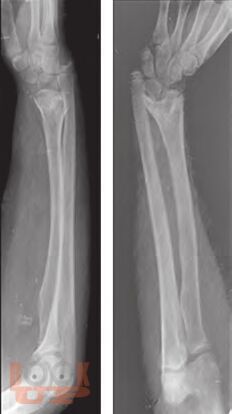

Ортопедические последствия гематогенного остеомиелита верхних конечностей у детей

Авторами представлен многолетний опыт лечения детей с ортопедическими последствиями гематогенного остеомиелита верхних конечностей. На основании комплексного обследования пациентов предложены оптимальные способы лечения детей с данной патологией.